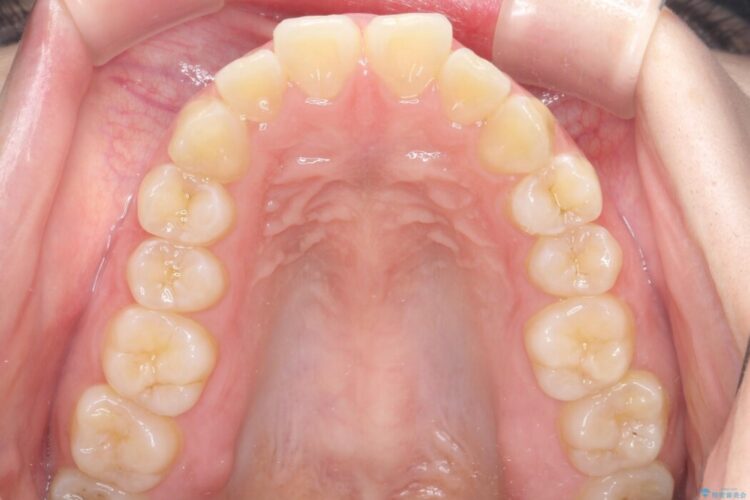

矯正検査の結果、前歯が外側に強く倒れ込んでいる「唇側傾斜(しんそくけいしゃ)」が認められ、口元の突出感の原因になっていました。

この傾斜を根本から正し、前歯を十分に後方へ下げるスペースを確保するため、上下左右の4番を抜歯し、目立ちにくい審美ワイヤー装置にて治療を行うこととしました。